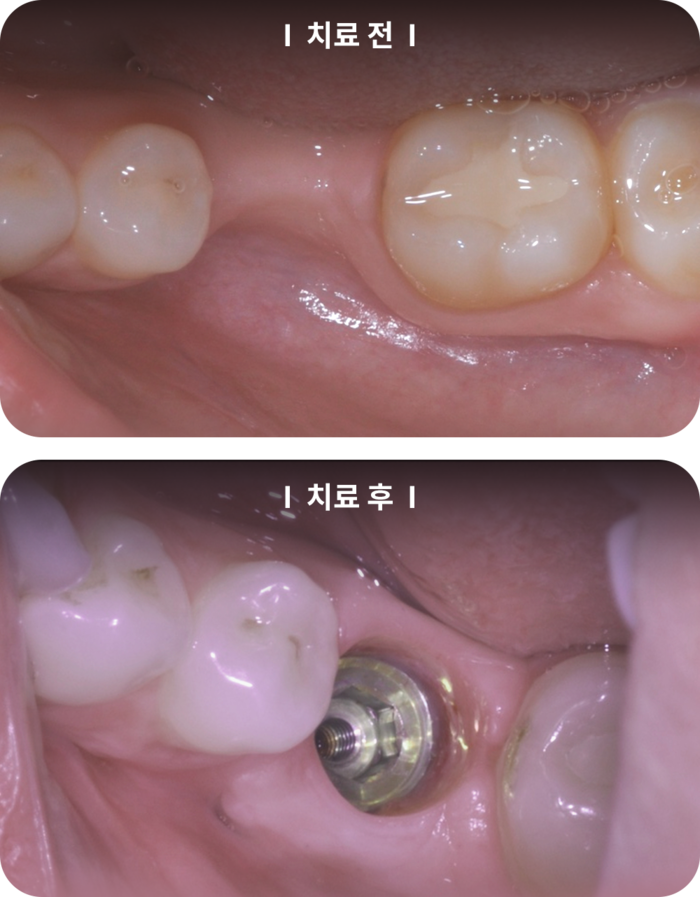

또한,

에서는 잇몸이식 수술을 받은 후의 모습을 보여줍니다. 치료 전의 사진에서는 잇몸이 내려앉아 있는 상태였던 반면, 치료 후에는 잇몸이 튼튼하게 재건된 모습을 확인할 수 있습니다. 이러한 사례들은 잇몸 치료가 얼마나 중요한지를 잘 보여줍니다.